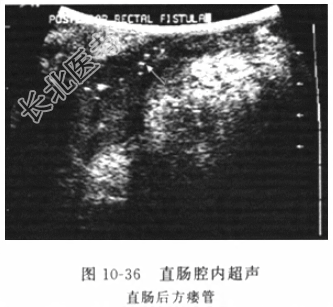

- [材料题] 患者男性,46岁,因“反复肛周左侧流脓血1个月余”入院。患者于1个多月前始间断出现肛门左侧流脓血水,有时伴肛周疼痛,当时未予重视,自行口服“头孢菌素”等“消炎”,症状有所好转,但不久又再度出现上述症状。本次就诊我院门诊,拟“肛瘘”收住入院。病程中无发热、寒战、便血、腹痛、腹泻、血尿等不适。发病以来,一般情况佳,大小便无异常。追溯病史,患者述1年前因“肛周脓肿”行手术切开治疗。体格检查体温(T)36.5℃,呼吸(R)18次/分,脉搏(P)72次/分,血压(BP)125/80mmHg。神志清楚,皮肤干燥,巩膜无黄染。腹部平坦,无压痛、反跳痛,肠鸣音无增强或减弱。膝胸位直肠检查:视诊(图10-35)见双侧臀部外形对称,肛门居中,膝胸位7点距肛缘1cm处见一0.3cm大小皮肤溃破口,指诊于7点处扪及条索样物直至对应肛窦处,直肠腔内未触及占位性病变,退出时指套无染血。辅助检查:血常规示白细胞8.9×10⁹/L,中性粒细胞80%,其他实验室检验结果包括肝肾功能、电解质和肿瘤标志物结果未见异常。全结肠镜检查未见结肠内病变,直肠超声内镜检查(图10-36)见直肠肛管后方瘘管。